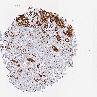

KRT17

CANCER BREAST CANCER Show tissue menu

BRCA TCGA BRCA VALIDATION PROTEIN EXPRESSION

ANTIBODIES

AND

VALIDATION